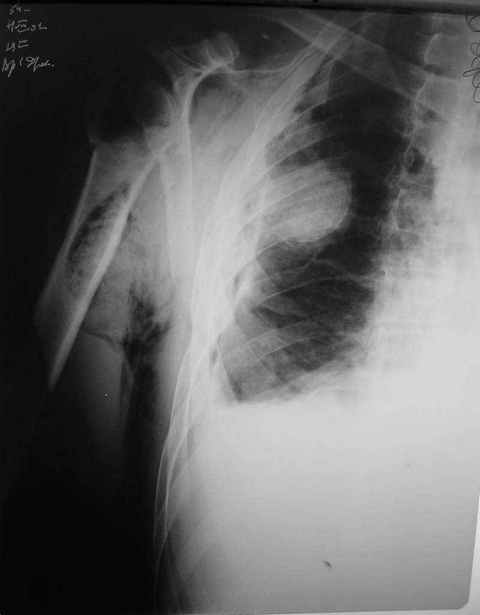

Александр, спасибо за столь высокую оценку. Нисколько не сомневаюсь, что и нам есть чему у Вас поучиться. Для иллюстрации прилагаю сегодняшний снимок с нашего обхода в шоковом зале реанимации (рис. 2).